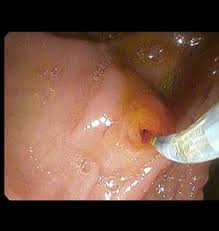

ERCP (Endoskopik Retrograt Kolanjio Pankreatigografi); Özel ışıklı bir aletle oniki parmak barsağında bulunan safra kanal ağzına kadar gelip, bu alet içinden geçirilen özel kanuller, kataterler aracılığı ile safra kanalları, safra kesesi, pankreas kanallarını görüntülemek ve gerektiğinde tedavi edici uygulamaların yapıldığı işlemdir.

- Tedavi amaçlı uygulamada ise ;taşların alınması,stent takılması, safra kanal ağzının açılması başlıcalarıdır